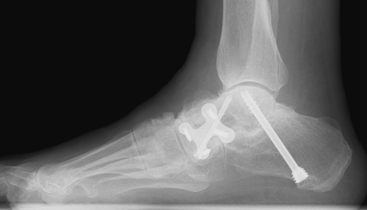

Rotational calcaneal osteotomy

This procedure combines some of the advantages of the Evans and the MDCO providing an increased ability to realign severe mal-alignment without fusing any joints.

There remains the risk in the adult patient of developing arthritis in other foot joints, depending on how well the individual adapts to the foot being repositioned. Other risks include nerve and tendon irritation due to the increased dissection and the proximity of these structures.

(Pre and post X-rays showing the line of the bone cuts and subsequently view post procedure with the calcaneum lengthened and rotated at the same time)